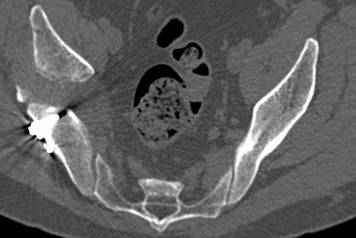

высылаю дополнительно сканы.

итак, второй вариант: высокий двухколонный с вовлечением КПС... Ни одно из основных повреждений не репонировано, кроме задней стенки. Скорее всего попытка реконструкции вертлуги сейчас будет очень травматичной и не очень эфективной, т.е. вероятный риск более значим, чем ожидаемая польза... Лучше подождать, и потом сразу эндопротез